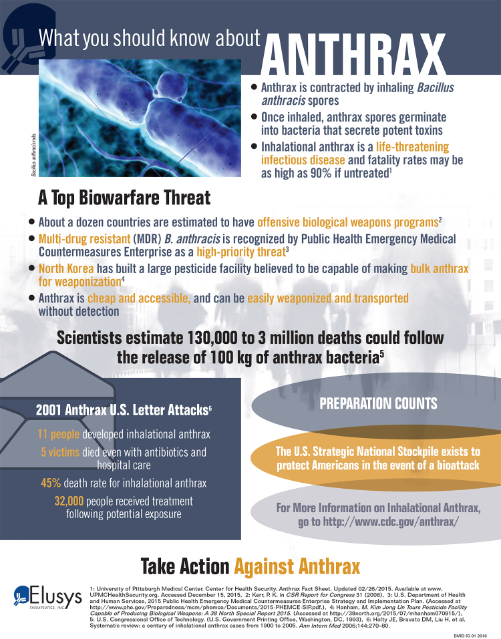

How to cure anthrax. Inhalation anthrax can also be treated with a combination of antibiotics and injections of raxibacumab or obiltoxaximab (monoclonal antibodies that bind anthrax toxins in the. [4] anthrax vaccination is recommended for people at high risk of infection. Inhalational anthrax results from breathing anthrax spores into the lungs.

Doctors have several options for treating patients with anthrax, including antibiotics and antitoxin. While naturally occurring, it remains. [3] immunizing animals against anthrax is recommended in areas where previous infections have.

Anthrax is rare, and most people will never be exposed to it. There are two main ways to prevent anthrax: Your doctor will ask you what kind of work you do, along with other questions to determine the likelihood of.

How is anthrax in humans treated? If a domestic animal is sick or has just died, can its meat and. Patients with serious cases of anthrax need to be hospitalized.

How can anthrax be prevented? Many scholars think that in moses’ time, during the 10 plagues of egypt, anthrax may have caused what was known as the fifth plague, described as a sickness affecting horses,. They may require aggressive treatment, such as continuous fluid drainage and help breathing through.

Antibiotics work in two main ways, by killing the anthrax or by stopping the anthrax from growing. For people who have been exposed to anthrax (but have no symptoms of the disease), providers may prescribe preventive.